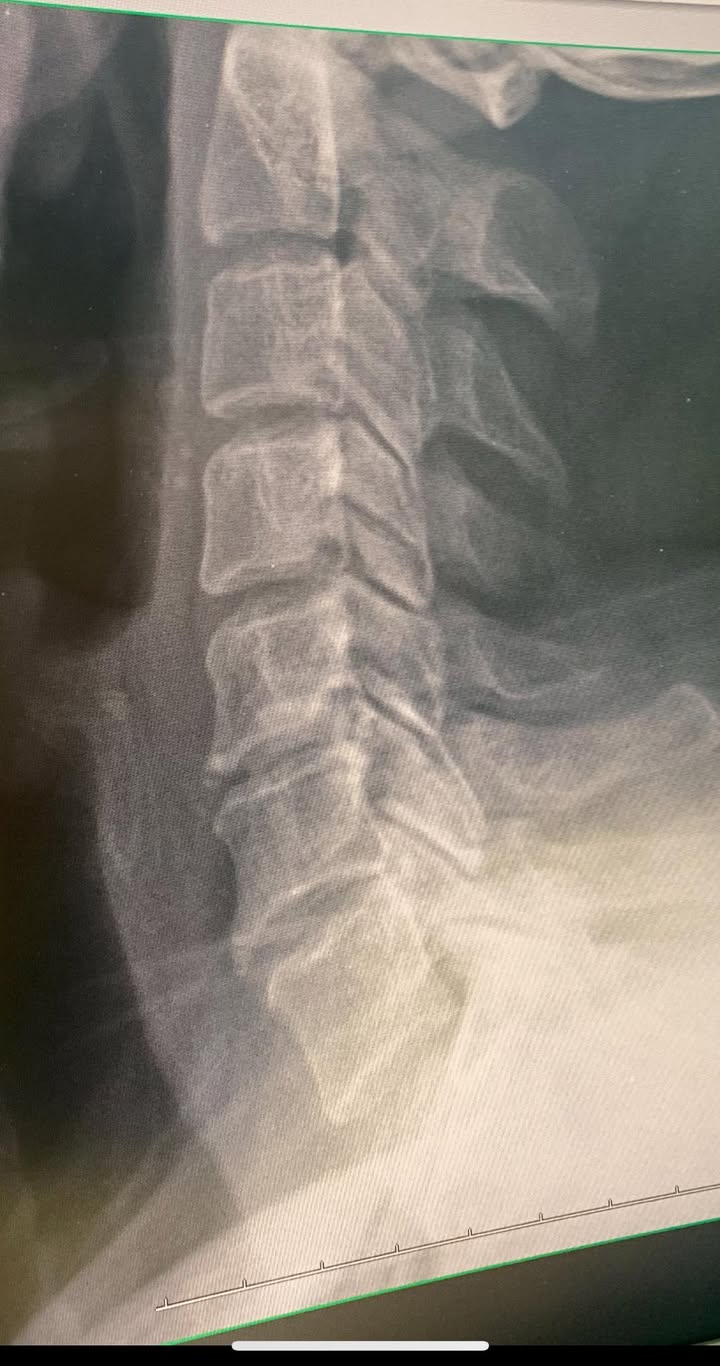

😂陳大哥在新莊開設汽車保養廠,由於今年累月的彎腰低頭修車不知不覺的頸椎跟肩膀開始明顯疼痛,酸痛的時間超過三年以上,在今年的12月開始接受治療,來診前已經有好幾個月痛到沒辦法睡覺,很典型的神經根卡壓患者,疼痛的區塊就是頸椎第五節神經根卡壓,比對一下最近拍的X光片側位照,很明顯的可以看到第五第六頸椎的間隙很狹窄,前面都長出骨刺,關節突的間隙也看起來很窄,頸椎的生理曲線也變直